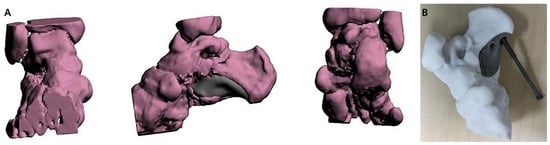

Preoperative 3D image rendering was generated based on CT data to assess the calcaneal defect and aid in designing a patient-specific prosthesis for reconstruction (Figure 2A). The rendered model was used for the 3D printing of a personalized prosthesis (Figure 2B).

Figure 2. 3D Surgical planning. (A) 3D image rendering from CT data used to simulate the calcaneal defect and design a personalized prosthesis for surgical reconstruction. (B) Clinical photograph of the 3D-printed prosthesis used for simulation.